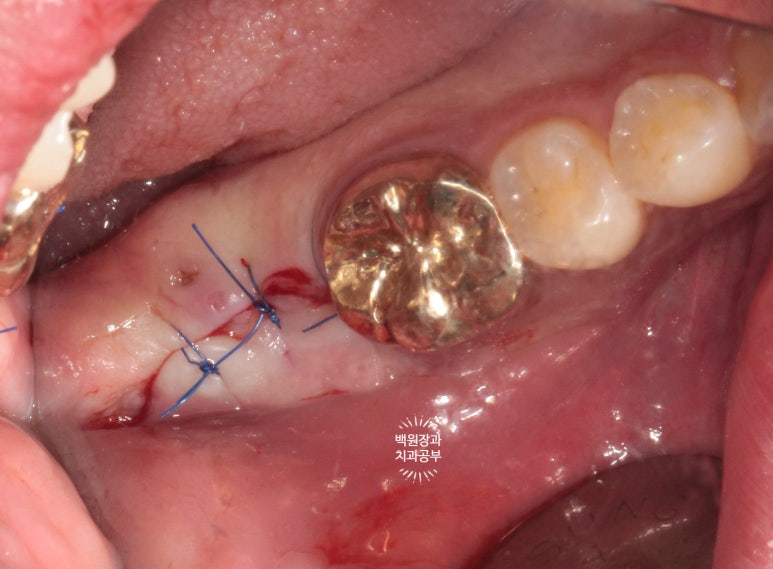

깔끔하게 꿰매드렸습니다.

사실 두 세 바늘 정도 꿰매는건, 솔직히 작은 수술입니다. 임플란트, 너무 두려워하지 마세요!!

15분도 안걸려 금방 마무리하였습니다.